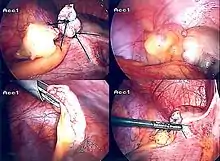

Laparoscopic appendectomy

Laparoscopic appendectomy was introduced in 1983 and has become an increasingly prevalent intervention for acute appendicitis.[80] This surgical procedure consists of making three to four incisions in the abdomen, each 0.25 to 0.5 inches (6.4 to 12.7 mm) long. This type of appendectomy is made by inserting a special surgical tool called a laparoscope into one of the incisions. The laparoscope is connected to a monitor outside the person's body, and it is designed to help the surgeon to inspect the infected area in the abdomen. The other two incisions are made for the specific removal of the appendix by using surgical instruments. Laparoscopic surgery requires general anesthesia, and it can last up to two hours. Laparoscopic appendectomy has several advantages over open appendectomy, including a shorter post-operative recovery, less post-operative pain, and lower superficial surgical site infection rate. However, the occurrence of an intra-abdominal abscess is almost three times more prevalent in laparoscopic appendectomy than open appendectomy.[81]